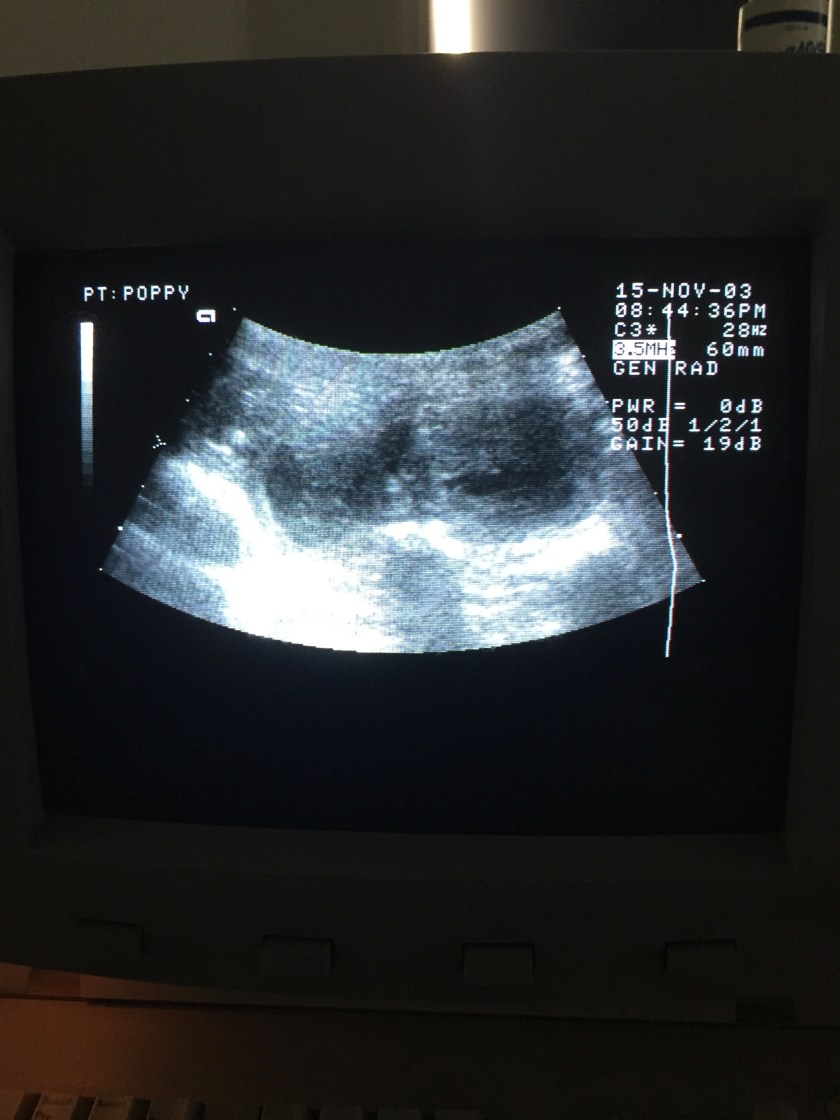

Poppy’s ultrasound on 19 December 2018. Her appointment was at 9.30am and Dr Bob Cavey of Ultimate Vet Clinic in Narre Warren confirmed her pregnancy. The small marble-like shapes in the centre are puppies! (Note: ignore the dates/times on the image)

19 December 2018 – Day 30

Poppy is now expecting! Bob Cavey counted 5 pups on one side and 4 on the other. There could be more tucked in behind her ribs but it won’t be possible to get a more accurate count until an X-ray at 8 weeks of pregnancy. Based on her progesterone tests in November and likely timing of ovulation, he estimates the due date to be 21 January 2019.